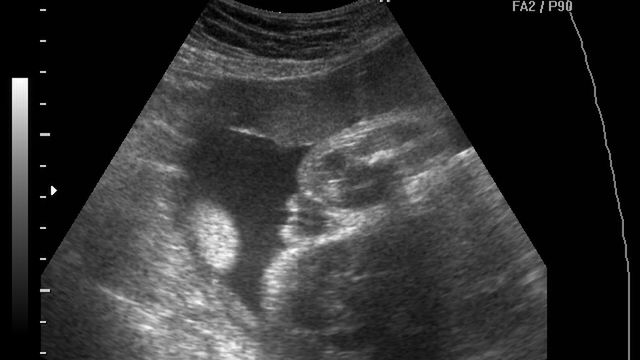

/ 10Zdjęcia płodu - 25 tydzień ciąży

Obraz

Płód w 25 tygodniu ciąży, na zdjęciu zaznaczony pęcherz moczowy dziecka